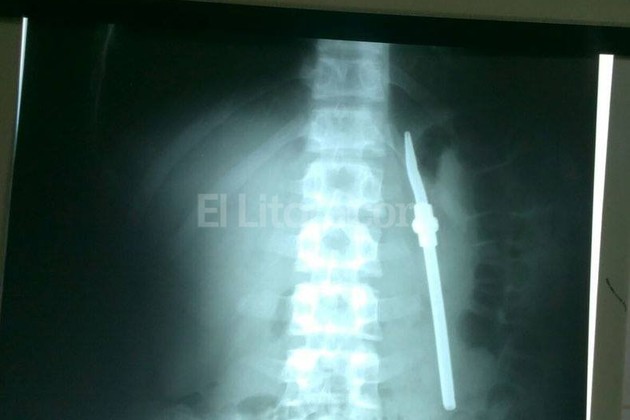

Un preso, que está alojado en la Unidad Penal n° 1 de Paraná, partió en dos una bombilla y se la tragó mientras tomaba mate junto a otros reclusos.

Según publica El Once, tras conocerse el episodio el sujeto fue derivado al hospital San Martín donde fue intervenido quirúrgicamente.

En declaraciones que reproduce el sitio entrerriano, el director del penal, Rubén Gómez, señaló: “En un momento de disconformidad, este sujeto partió la bombilla y se la tragó. Testigos que estaban en el lugar no se explican por qué lo hizo”.